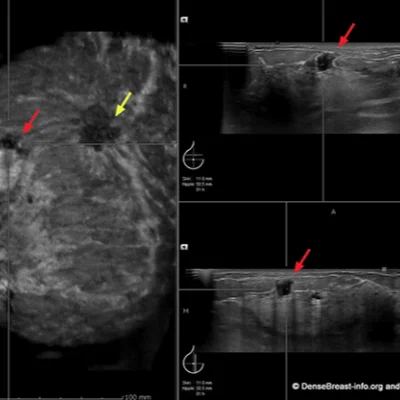

Breast

Evaluate lumps, cysts, or post-mammography findings